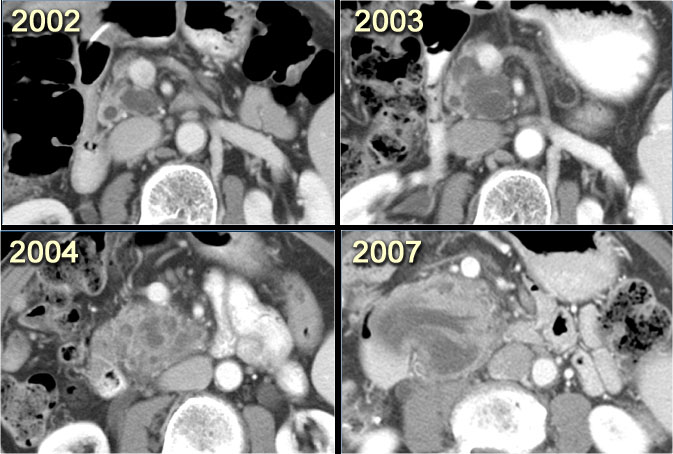

CT-images of a patient with a branch-duct IPMN who choose not to have surgery.

Over time growth of the tumor is seen with dilatation of the main duct indicating malignant transformation.

Sometimes it takes 5-8 years before a transformation is seen.